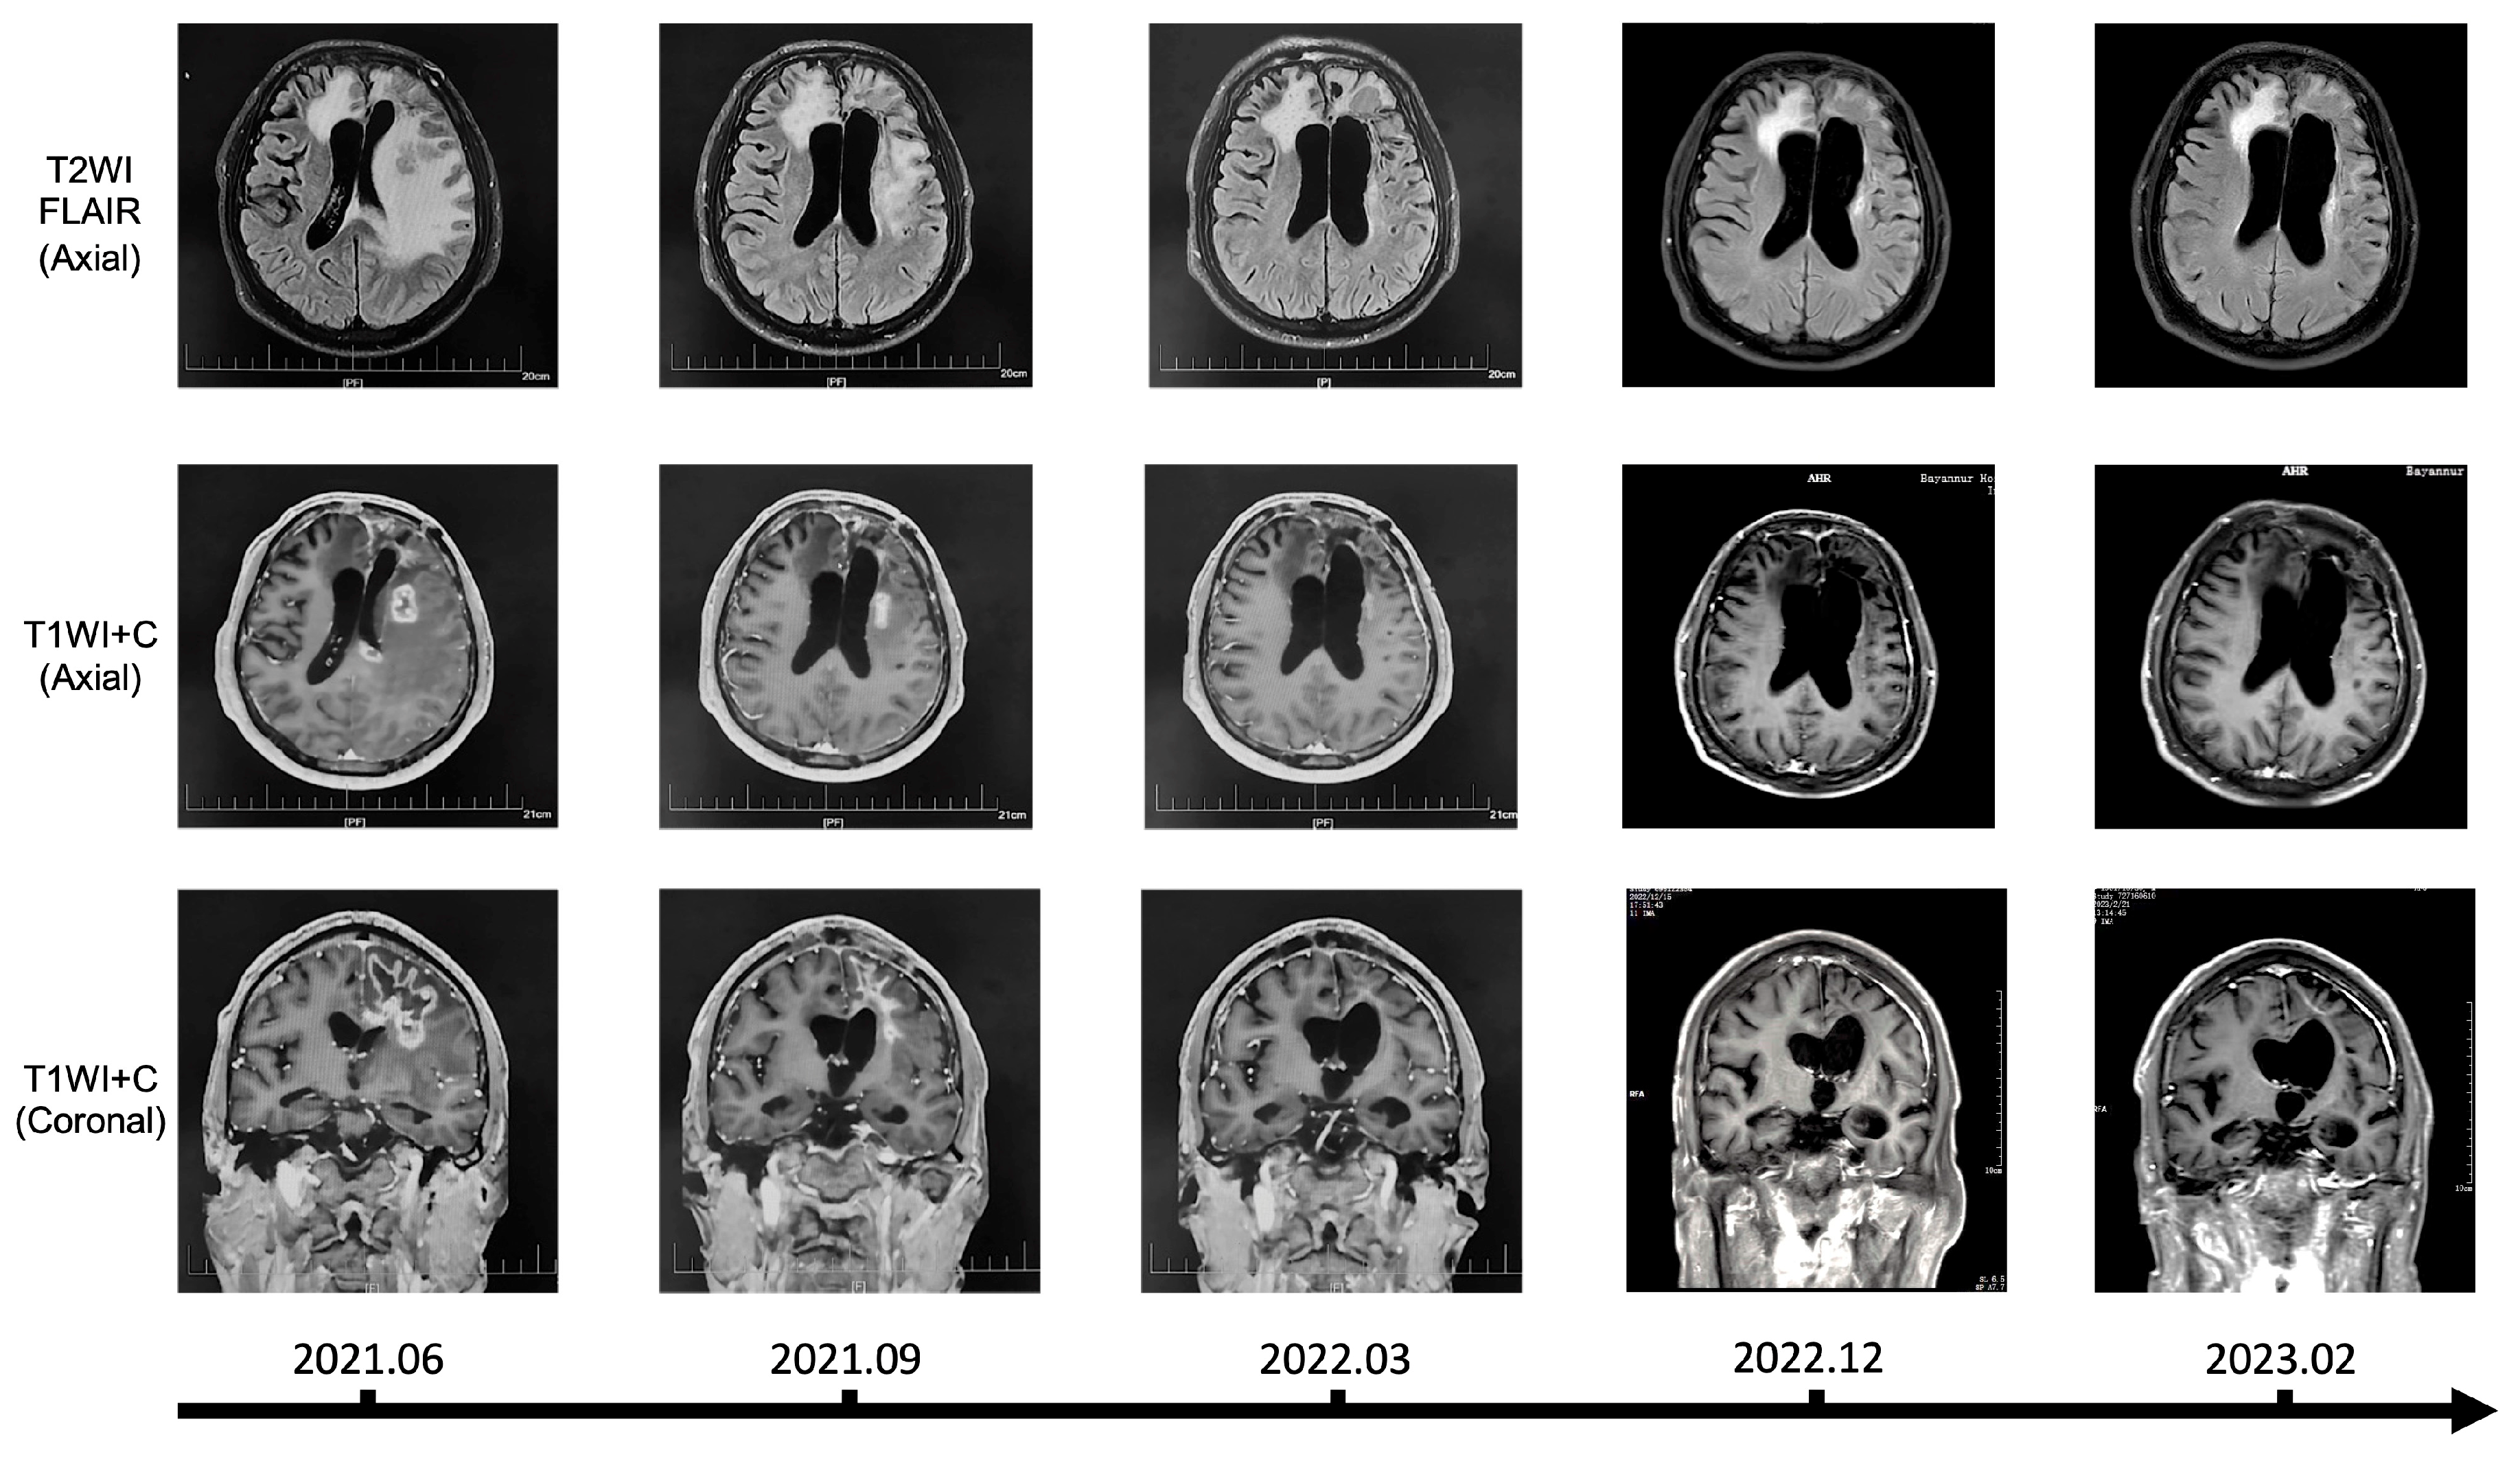

3.8. Clinical Application of Chlorogenic Acid in the Treatment of Recurrent Glioma Patients